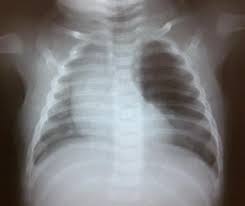

Para llegar a un diagnóstico preciso, la radiografía de tórax inicial es fundamental. En ella se observa un lóbulo hiperinsuflado e hiperlúcido (muy oscuro por la acumulación de aire) que empuja la tráquea y el corazón hacia el lado sano, provocando desviación mediastínica. Un detalle clave es que mantiene marcas vasculares finas, lo que es vital para diferenciarlo rápidamente de un neumotórax a tensión, una emergencia mortal que no presenta ninguna marca vascular en la placa.